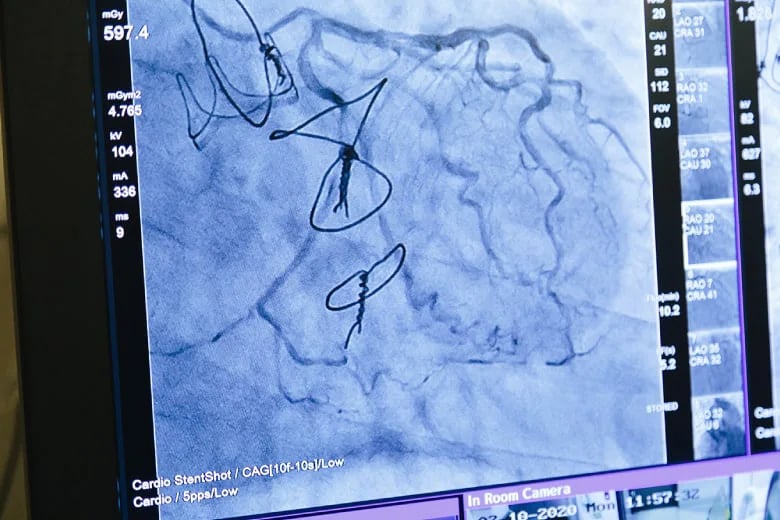

Dr. Horrigan has especially seen the need for Yuki in the catheterization laboratory, or “cath lab”, he directs at Austin Health in Melbourne, Australia. Some patients will visit the cath lab to have their heart and vasculature evaluated, while others need further intervention to correct narrow arteries or defective heart valves. Whatever the reason, the doctor will pass a catheter into the patient’s blood vessels through the arm or groin all the way to the heart. In rare cases, the patient may suffer from bleeding or blood clots, but in general the patient should leave in no worse condition than as if visiting the dentist. However, research has repeatedly shown that catheterization procedures can leave patients with damage to completely different organs, namely, the kidneys and skin 1.

This damage is caused by the contrast agents and X-rays used during the procedure, but the damage has no immediate symptoms, and the patient is discharged before they or the clinical staff are aware of any trouble.